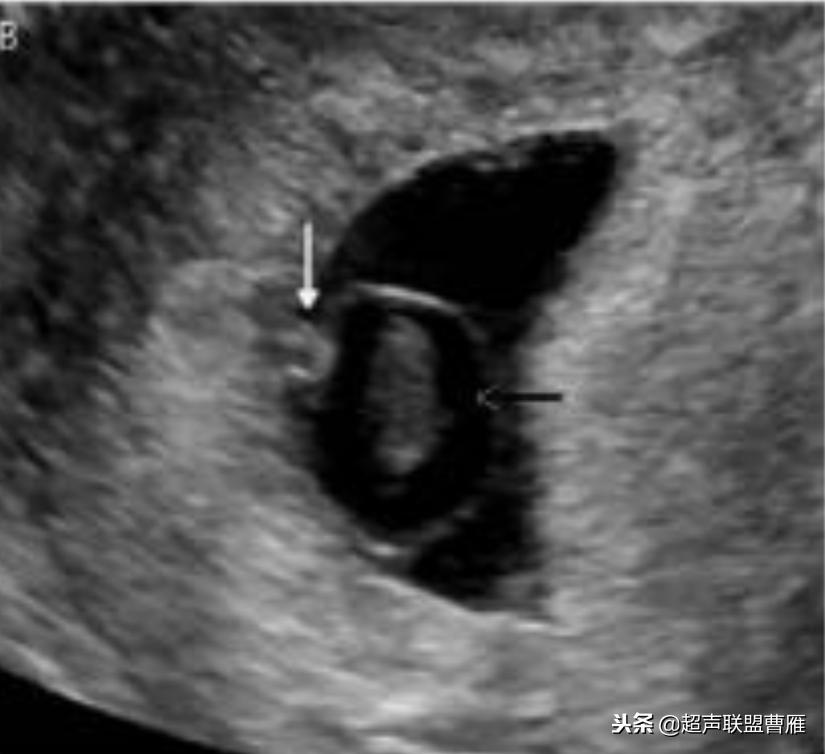

正常早孕卵黄囊声像图

早孕 胚芽 卵黄囊

5周+ 、6周+ 声像图

孕7周左右(胚芽11mm 卵黄囊)